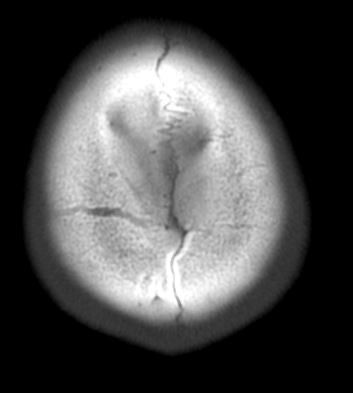

두개골 수술 또는 골절 의심되는 상황인데 엑스레이와 ct사진을 한번 봐주실 수 있나요?

2~3일 정도 기억이 없었는데 그때 머리를 다쳤는지 바로 x-ray와 ct를 찍어봤는데 한번 봐주실 수 있을까요? 진단 목적이 아닌 확인 목적입니다

빨갛게 동그라미 친 곳은 금속물질이 의심도는 부근입니다

• 1번 째 사진